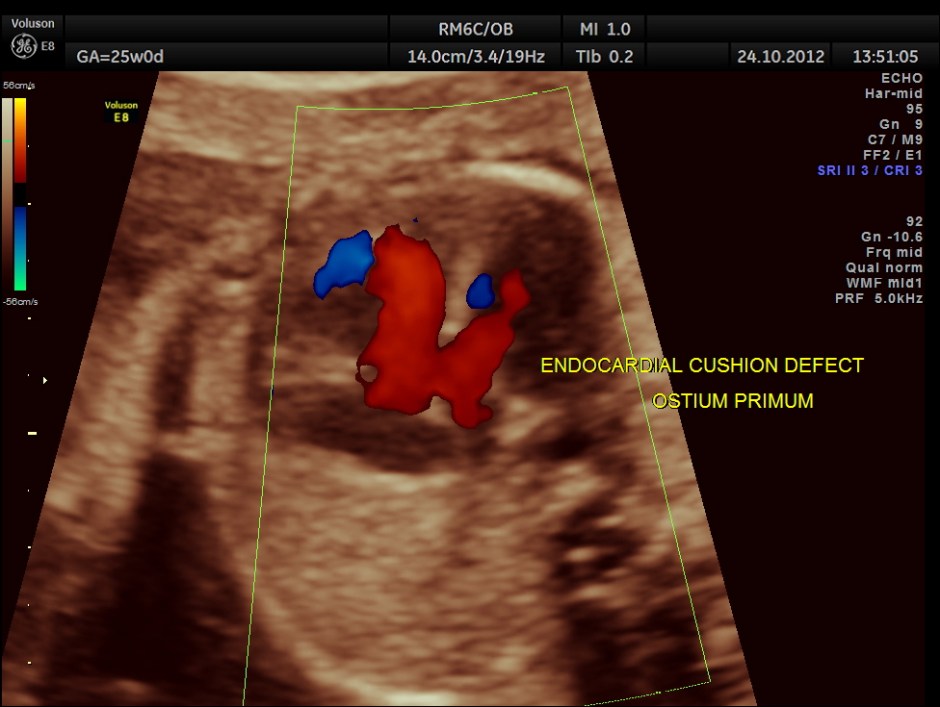

The scan was done around 25 weeks of gestation :

colour flow clearly demonstrating the atrio ventricular septal defect